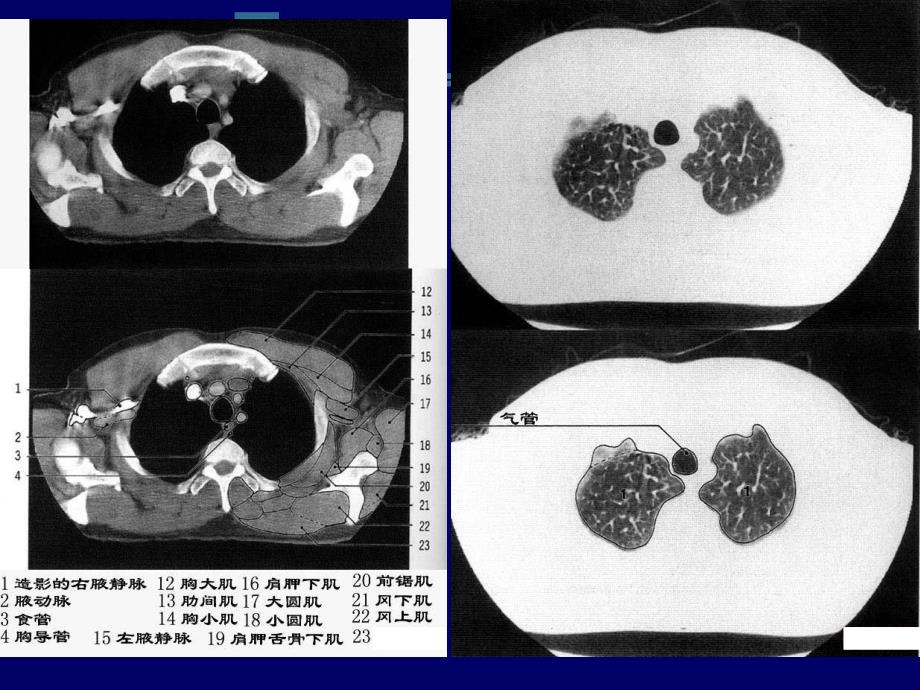

CT胸部解剖